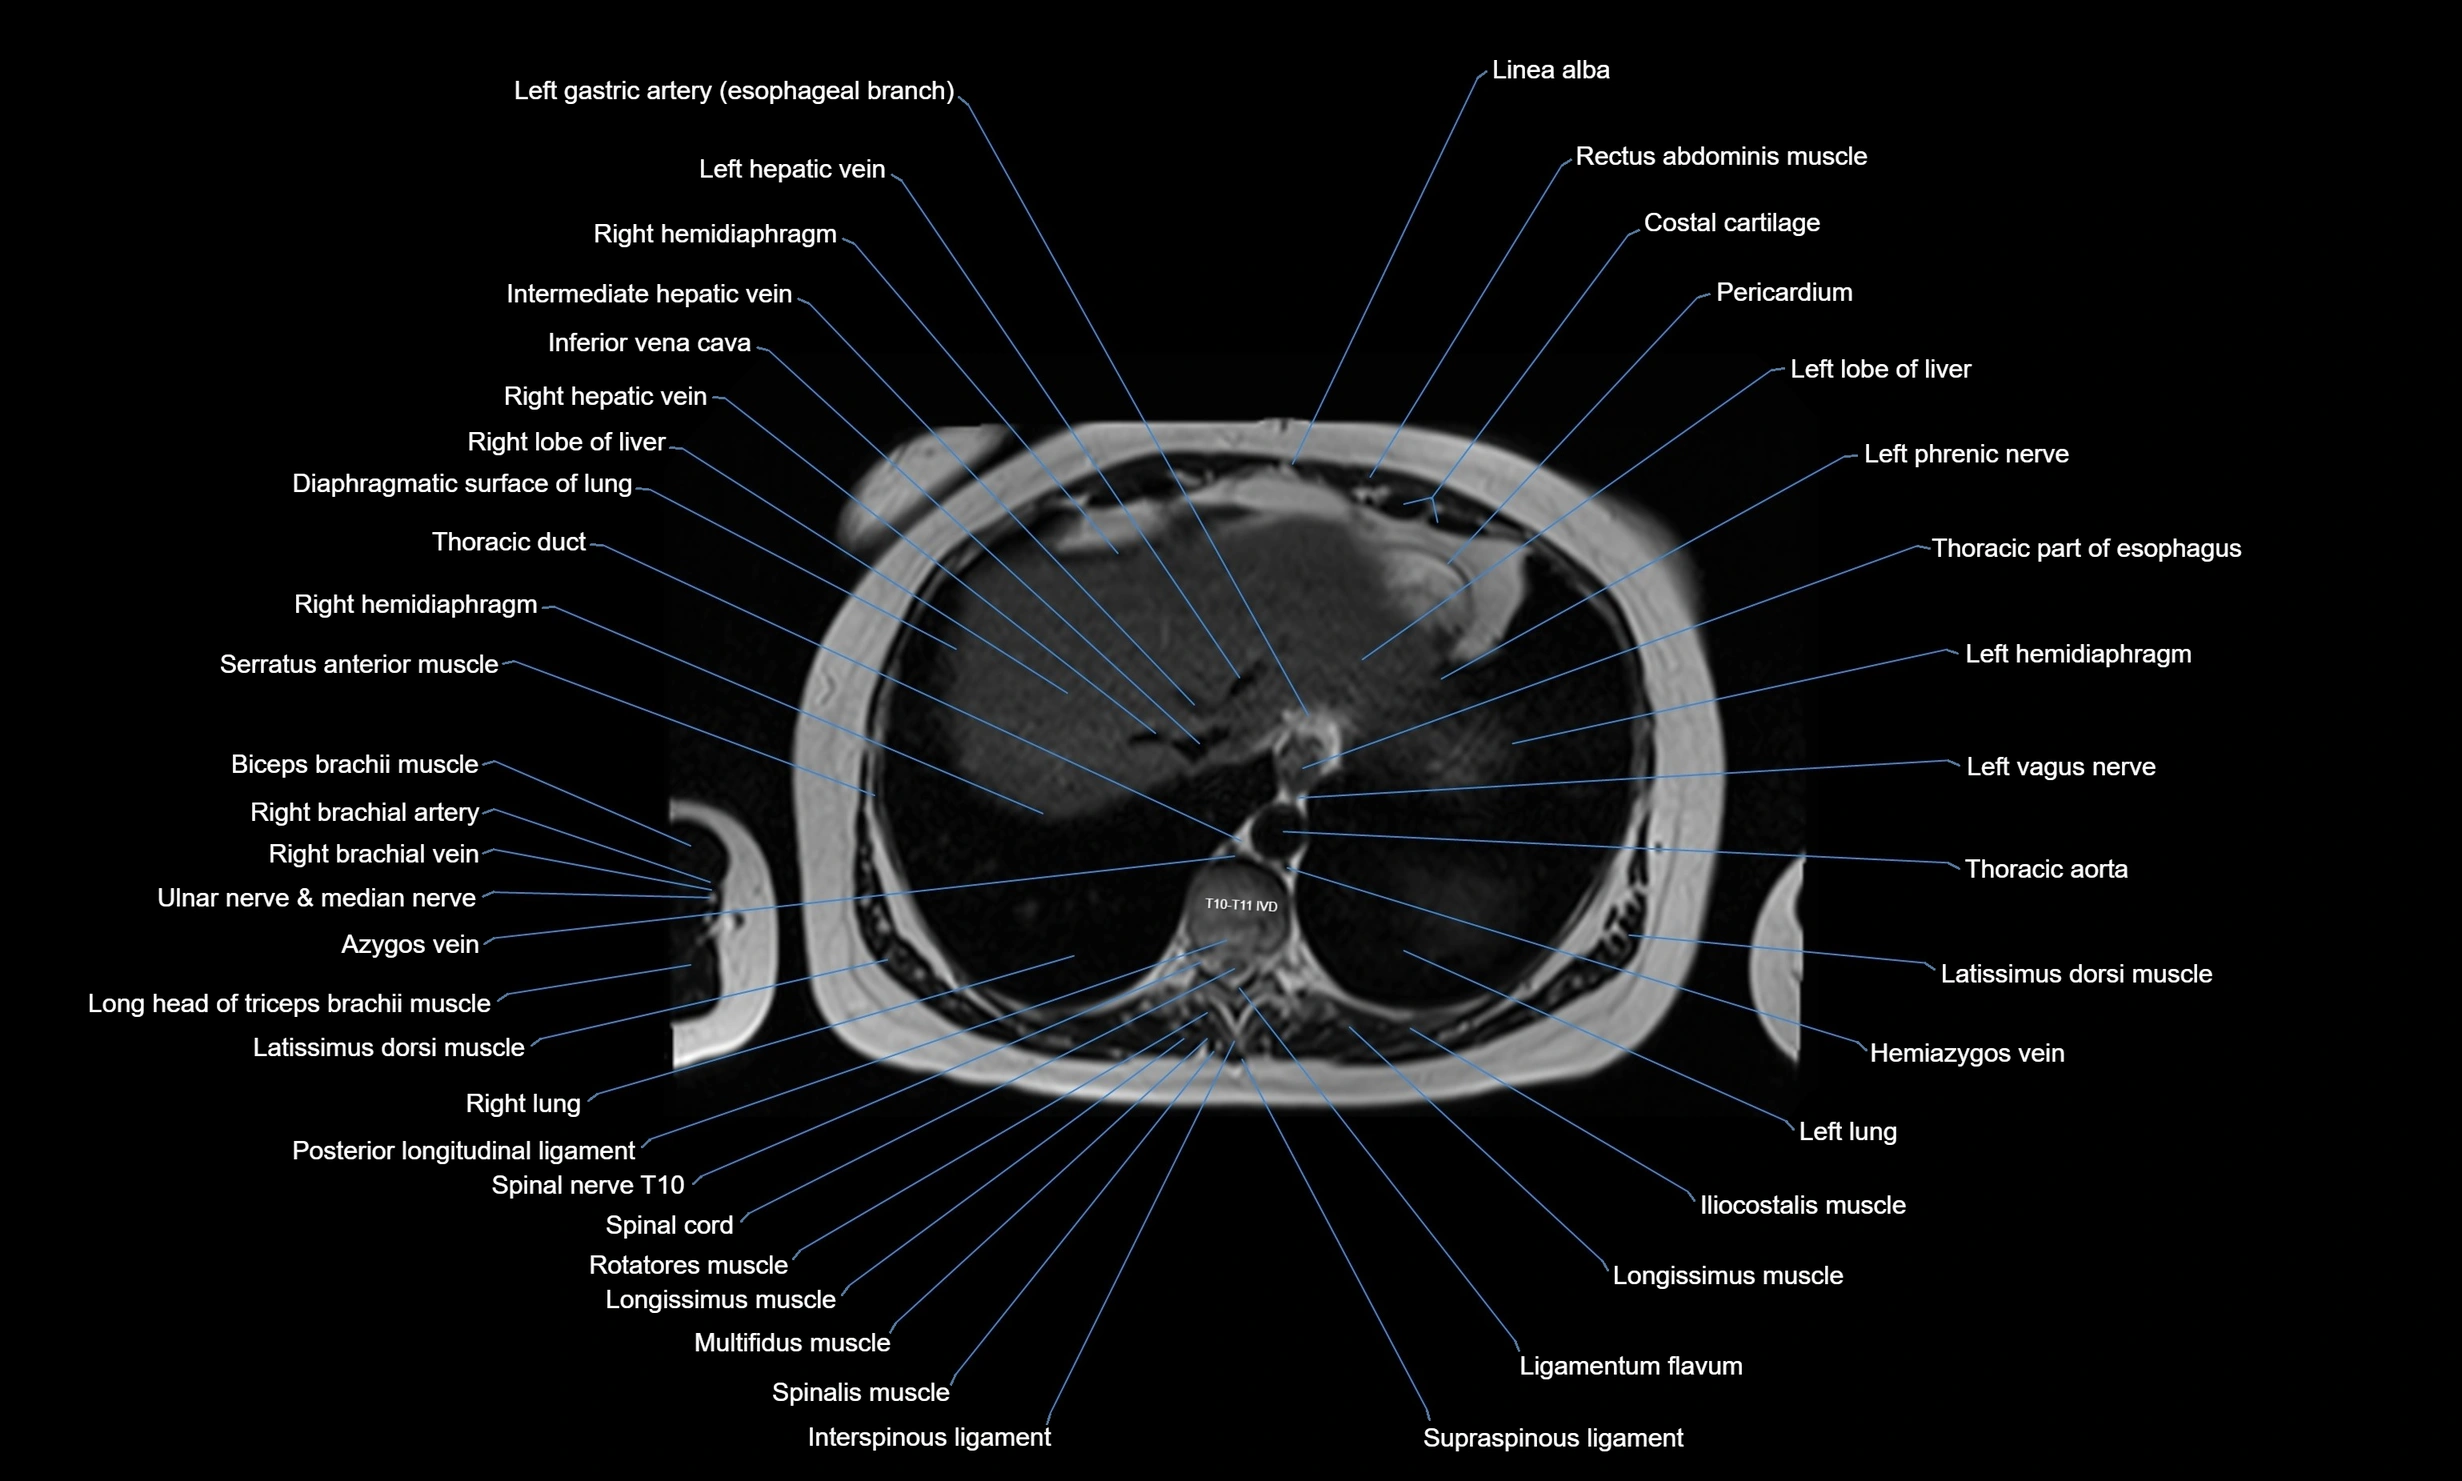

MRI images